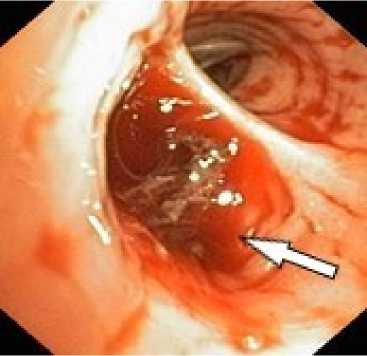

Первым этапом в процессе диагностики бронхоскопии через фибробронхоскоп выполняли промывание трахеи холодным физиологическим раствором, инъекции адреналина (рис. 5). При наличии и доступности определённого источника кровотечения использована электрокоагуляция с ис- сечением опухоли бронха 4 (2,7%), бужирование и стентирование бронха 11 (7,3%). При интенсивном кровотечении в 13 (8,7%) случаях выполняли брон-хоблокацию. Удаление блокатора осуществляли на 5–8 сутки. В одном случае бронхоблокация сочеталась со стентированием аорты. Проведённый анализ ангиограмм позволил выявить косвенные признаки ЛК. В большинстве случаев наблюдалось усиление кровоснабжения зоны поражения независимо от выявленной патологии (рис. 6, а). Локализация сосудистых изменений соответствовала данным, полученным при таких диагностических методах как ФБС и КТ. Эти ангиографические признаки не имеют прямого отношения к ЛК, но достаточно полно характеризуют его причину в силу специфичности семиотики различных лёгочных заболеваний. Прямые признаки экстравазации мы наблюдали в одном случае при наличии аортобронхиального свища (рис. 9, а).

Рисунок 5. Эндоскопическая картина лёгочного кровотечения. Источник кровотечения – бронх В3 справа и средне-долевой бронх правого лёгкого: а – кровь в просвете бронха В3 справа; б – кровь в просвете средне-долевого бронха справа

Figure 5. Endoscopic view of pulmonary hemorrhage. Bleeding source: B3 bronchus on the right and middle lobe bronchus of the right lung: a – blood in the lumen of the right B3 bronchus; б – blood in the lumen of the right middle lobe bronchus